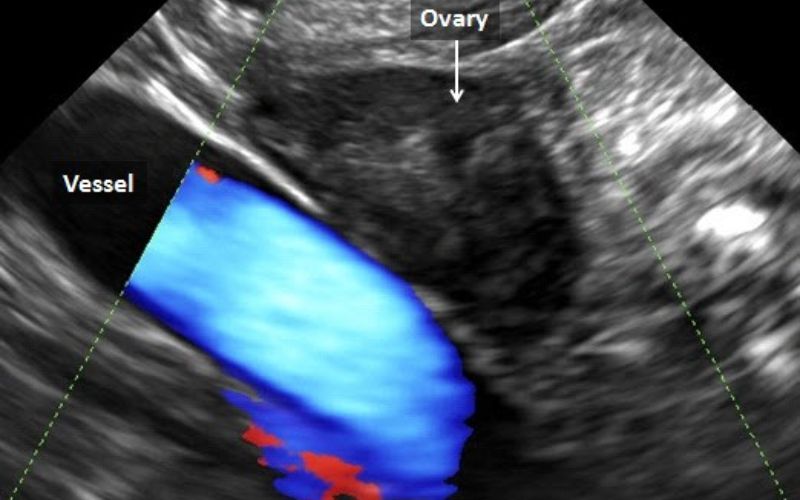

Thực tế, Siêu âm có phát hiện tắc vòi trứng không phụ thuộc vào tình trạng cụ thể. Siêu âm thường chỉ thấy được Hình ảnh ứ dịch vòi trứng (khi vòi trứng sưng to chứa dịch). Để chẩn đoán chính xác vòi trứng có thông hay không, bác sĩ bắt buộc phải chỉ định chụp tử cung vòi trứng (HSG).

Thông qua Hình ảnh ứ dịch vòi trứng trên siêu âm đầu dò hoặc chụp HSG, bác sĩ sẽ đánh giá mức độ nghiêm trọng.